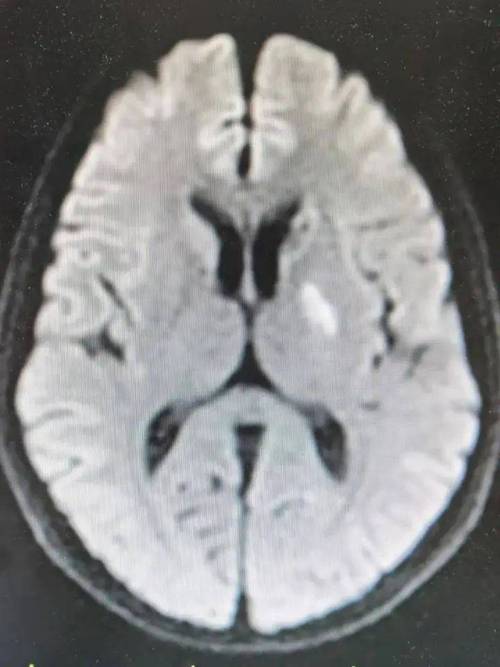

(图片来源网络,侵删)

- 什么是脑梗病灶? 脑梗,全称“脑梗死”或“缺血性脑卒中”,是指因为脑部血管堵塞,导致局部脑组织缺血、缺氧而发生的坏死,这个坏死区域,在影像学检查(如CT或MRI)上显示出来的“印记”,脑梗病灶”,它就像身体其他部位(如心脏)的“心梗”一样,是脑组织受损后留下的痕迹。

- “多处”意味着什么? “多处”说明这种血管堵塞事件不是第一次发生,而是可能已经发生过多次,只是之前没有症状或者症状轻微未被察觉,每一次堵塞都会留下一个病灶,这提示我们,导致血管堵塞的根本原因依然存在,并且正在持续对大脑造成损害,核心任务是找到并控制这个“根本原因”。

- 头颅MRI+DWI+MRA/CTA: MRI是发现脑梗病灶最敏感的检查,MRA(磁共振血管成像)或CTA(CT血管成像)可以查看脑血管有无狭窄或闭塞。